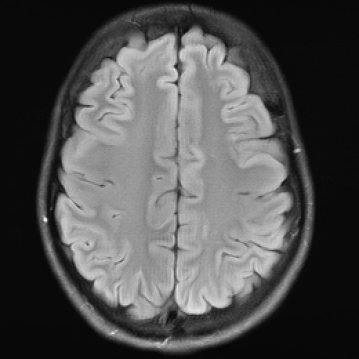

3.2.2 Example 1: Scan acceleration

The reconstructions in Figure 5 were obtained by the application of E2E-VarNet, Figure 5 (b)(c)(e)(f), and XPDNet, Figure 5 (a)(d), to accelerated data with random masks (acceleration factor between 1 to 5) in the frequency domain.

Refer to caption

(a) (27.8, 0.78, 0.14)

(b) (29.6, 0.85, 0.14)

(c) (32.3, 0.92, 0.04)

(d) (29.5, 0.84, 0.12)

(e) (29.6, 0.86, 0.12)

(f) (33.0, 0.94, 0.04)

Figure 5: Reconstruction outputs of accelerated FLAIR MRI data from the algorithms Xpdnet(a)(d) and E2varnet (b)(c)(e)(f). The bottom images (d)-(f) are judged by PSNR/SSIM/LPIPS as better reconstructions than the respective image above them (a)-(c), although visually they clearly have worse quality.

FR-IQA mismatch

We can see in Figure 5 that the visual quality of the obtained images does not correspond to the numbers provided by PSNR/SSIM/LPIPS. This is not surprising as some challenges with SSIM as a performance metric have already been discussed in the official results paper of the challenge (citep \@BBN(Muckley et al., 2021a)) and small artefacts/wrong lesions have been shown. Here, we complement with examples where the visual results clearly ask for a different judgement even in a non local manner. In particular, the bottom images in Figure 5 show stronger artefacts and loss of information in comparison to the images on top. In addition, the degraded images (e) (f) do hold quite higher numbers in comparison to (a) which is nearly noise-free.